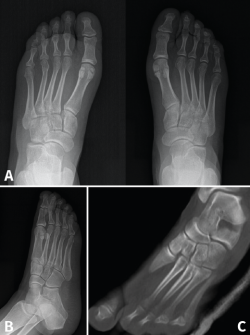

Figura 5. Resultados radiográficos posquirúrgicos en el caso 1.

Figura 6. Resultados radiográficos posquirúrgicos en el caso 2.

La revisión a los 3 meses mostró resultados satisfactorios en ambos casos, con tolerancia de la carga completa. Además, las imágenes radiológicas demostraron el mantenimiento de la reducción conseguida en el quirófano, sin movilización del material (Figuras 5 y 6).

En el primer caso, la incorporación laboral fue a los 4 meses y, en el segundo caso, a los 6 meses; los pacientes no presentaron dolor. A los 10 meses postoperatorios el examen clínico no reveló evidencia de dolor en la zona quirúrgica y los pacientes habían reanudado todas sus actividades regulares, incluida la práctica deportiva, sin complicaciones. Además, las radiografías en ese momento revelaron una reducción anatómica de la lesión.